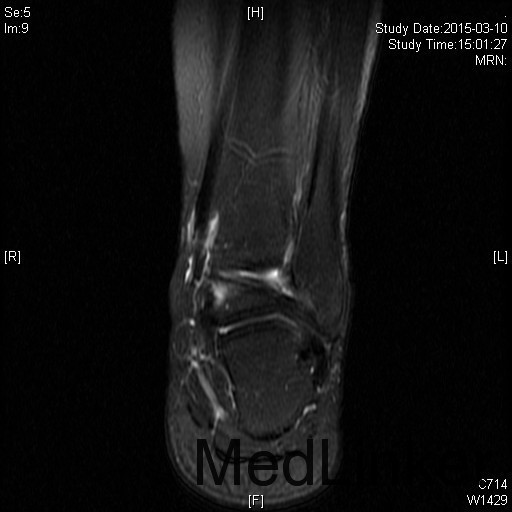

左踝扭伤后肿胀疼痛伴活动受限半年

查体:左腓肠肌萎缩,左踝轻度肿胀。左踝关节ROM较对侧降低,以背伸活动受限最明显。距腓前韧带处未及明显压痛。左踝内、外侧关节间隙压痛(+)。ADT(-),外侧应力试验(-)。左下肢肌张力正常、感觉正常。 辅检:MRI示“左踝关节积液”

诊断:左踝关节创伤性滑膜炎 治疗:左踝关节镜下滑膜清理、胫骨前缘成形

随访:患者术后即刻踝关节活动度恢复正常,2周恢复正常行走。 讨论:踝关节扭伤很常见,扭伤后会发生各种各样的情况。此患者扭伤后继发了滑膜炎,并伤及了关节软骨。这种情况应进行关节镜手术治疗。此外,核磁共振对关节疾患的诊断也是有限的,关节镜才是黄金标准。